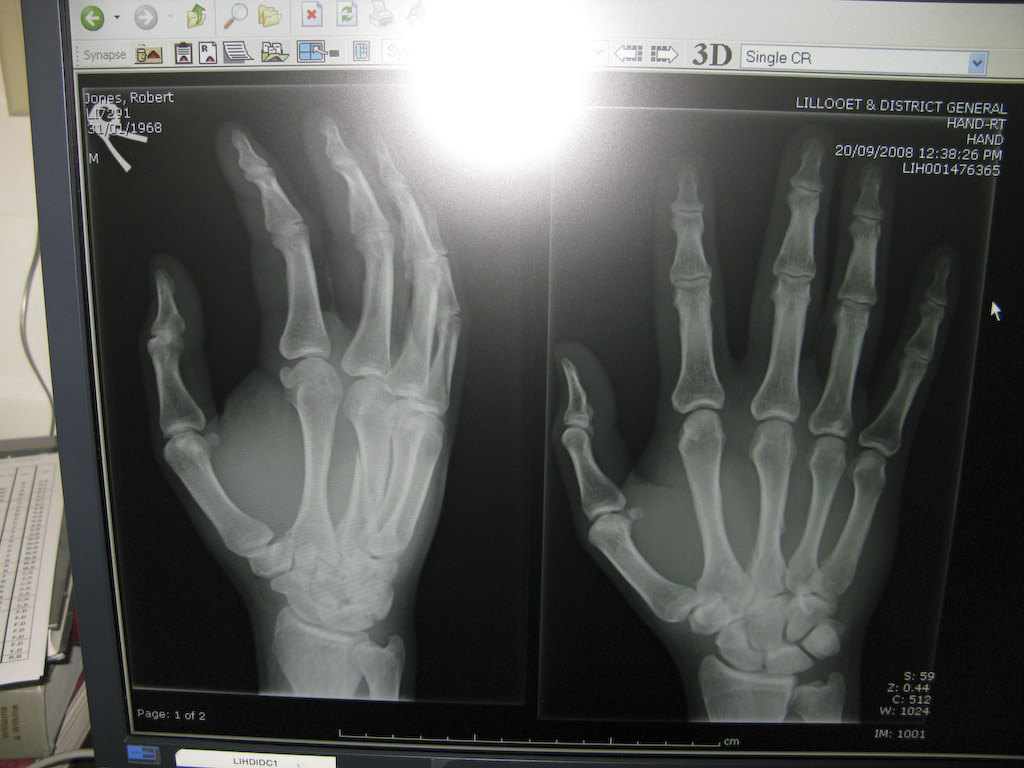

Awwwwwwwwww….I think summer is finally over. Cold and wet this morning. A few of us are taking the day off to go to Lillooet. I gues somebody kind of needs some X-rays (a bug blue hand this morning).

Just kidding, that’s Rob’s hand. If you look close you’ll see a nice spiral fracture of his driving finger. What a bummer.